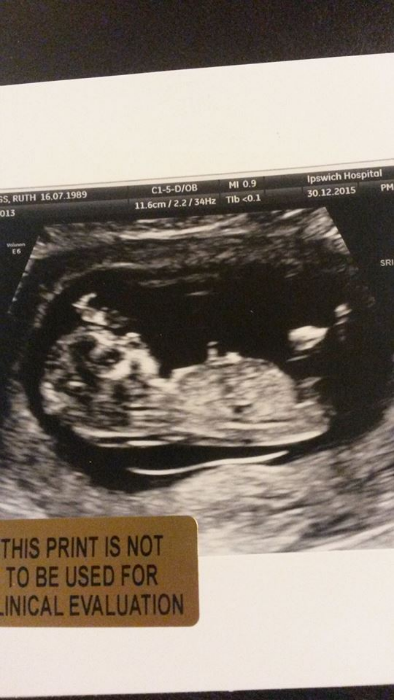

The first picture of our unborn child.